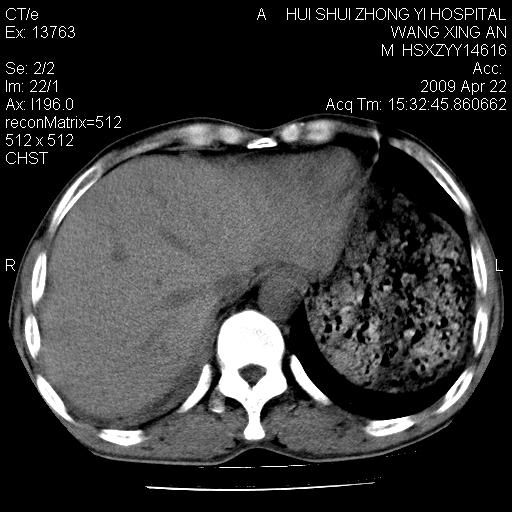

标题: CT19534:患者男、46岁咳嗽、胸痛半月。 [打印本页]

标题: CT19534:患者男、46岁咳嗽、胸痛半月。

1、右下肺中央型肺癌并右肺转移,右肺下叶不张。(肿块围绕右肺下叶支气管生长,致管腔闭塞右肺下叶不张;右肺有结节影)。

2、右侧胸腔积液。

3、右中上肺陈旧性肺结核(右肺见纤维化病灶及点状钙化)。

1、右下肺中央型肺癌并右肺转移,右肺中下叶不张。(右肺有结节影)。胸骨转移

2、右中上肺陈旧性肺结核(因为大多为纤维灶)。

3、右侧胸腔积液。

1)右肺中间段支气管癌并右肺下叶肺不张。2)右肺上叶、两肺下叶背段感染性病变。3)右侧少量胸腔积液。